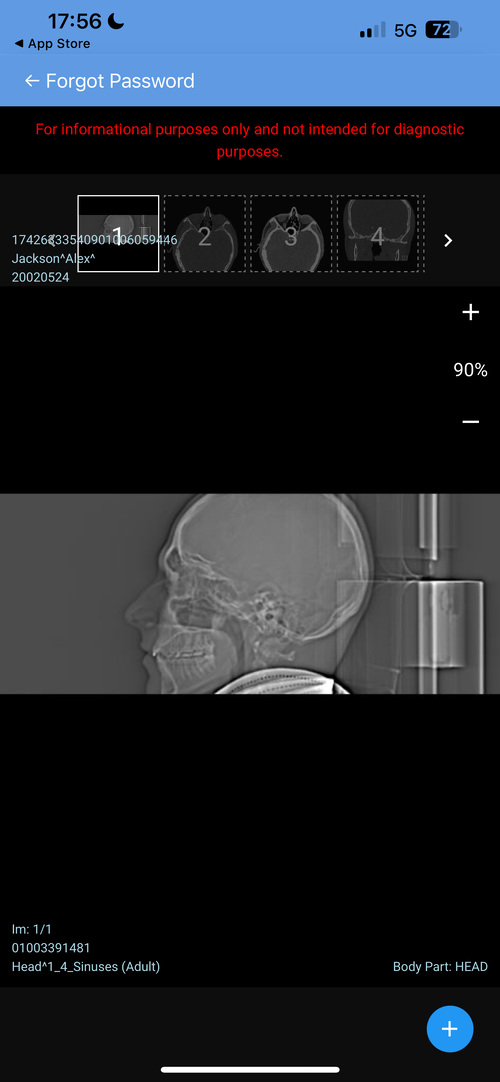

Hello, I’m looking for advice on genioplasty vs DJS. I was planned for a genio 7mm horizontal and squaring of chin on may 11th. I got a second opinion because I thought the oralmaxillofacila surgeon doing my genio might have been downplaying my mandible/maxilla recession. The second opinion oomfs surgeon said that genio would only be a camouflage and for my high expectations, might disappoint me, and I’m starting to think it will. My midface is flat and my mandible from side profile looks short and awful. The problem I have is DJS is a huge commitment for a bigger gain in a year-year and a half time. It’s a lot to take in. But I really don’t want to live my whole life with recessed jaws, I don’t want a soft youthful boyish look especially because I’m getting into my mid 20s, I hate my side profile a lot. Genio will help but I’m extremely worried I’ll be really disappointed, and I can’t really go back if I commit. Looking for advice on if I should go with the genio, see improvement now (which I care a lot about) and get a rhino/septoplasty to fix my deviated septum and be capped by by midface/mandible recession but decently improved, or If I should look awful for another year and a half with braces and my current recession but have the functional and aesthetic benefit of djs at the end. I have extremely bad breathing issues especially during exercise and pretty bad sleep issues, but I don’t know how much to that is down to allergies/deviated septum as opposed to airway issues. I just don’t know what to do, I’ll include my ceph/ct scans and side/front profile photos, would really appreciate guidance on what to do, was thinking of frauding with filler for a year before getting djs, or getting real structural change through rhino braces and genio that would all be down within 7-9 months, thankyou .

• IMG_0339.png

IMG_0339.png

612.1 KB · Views: 0